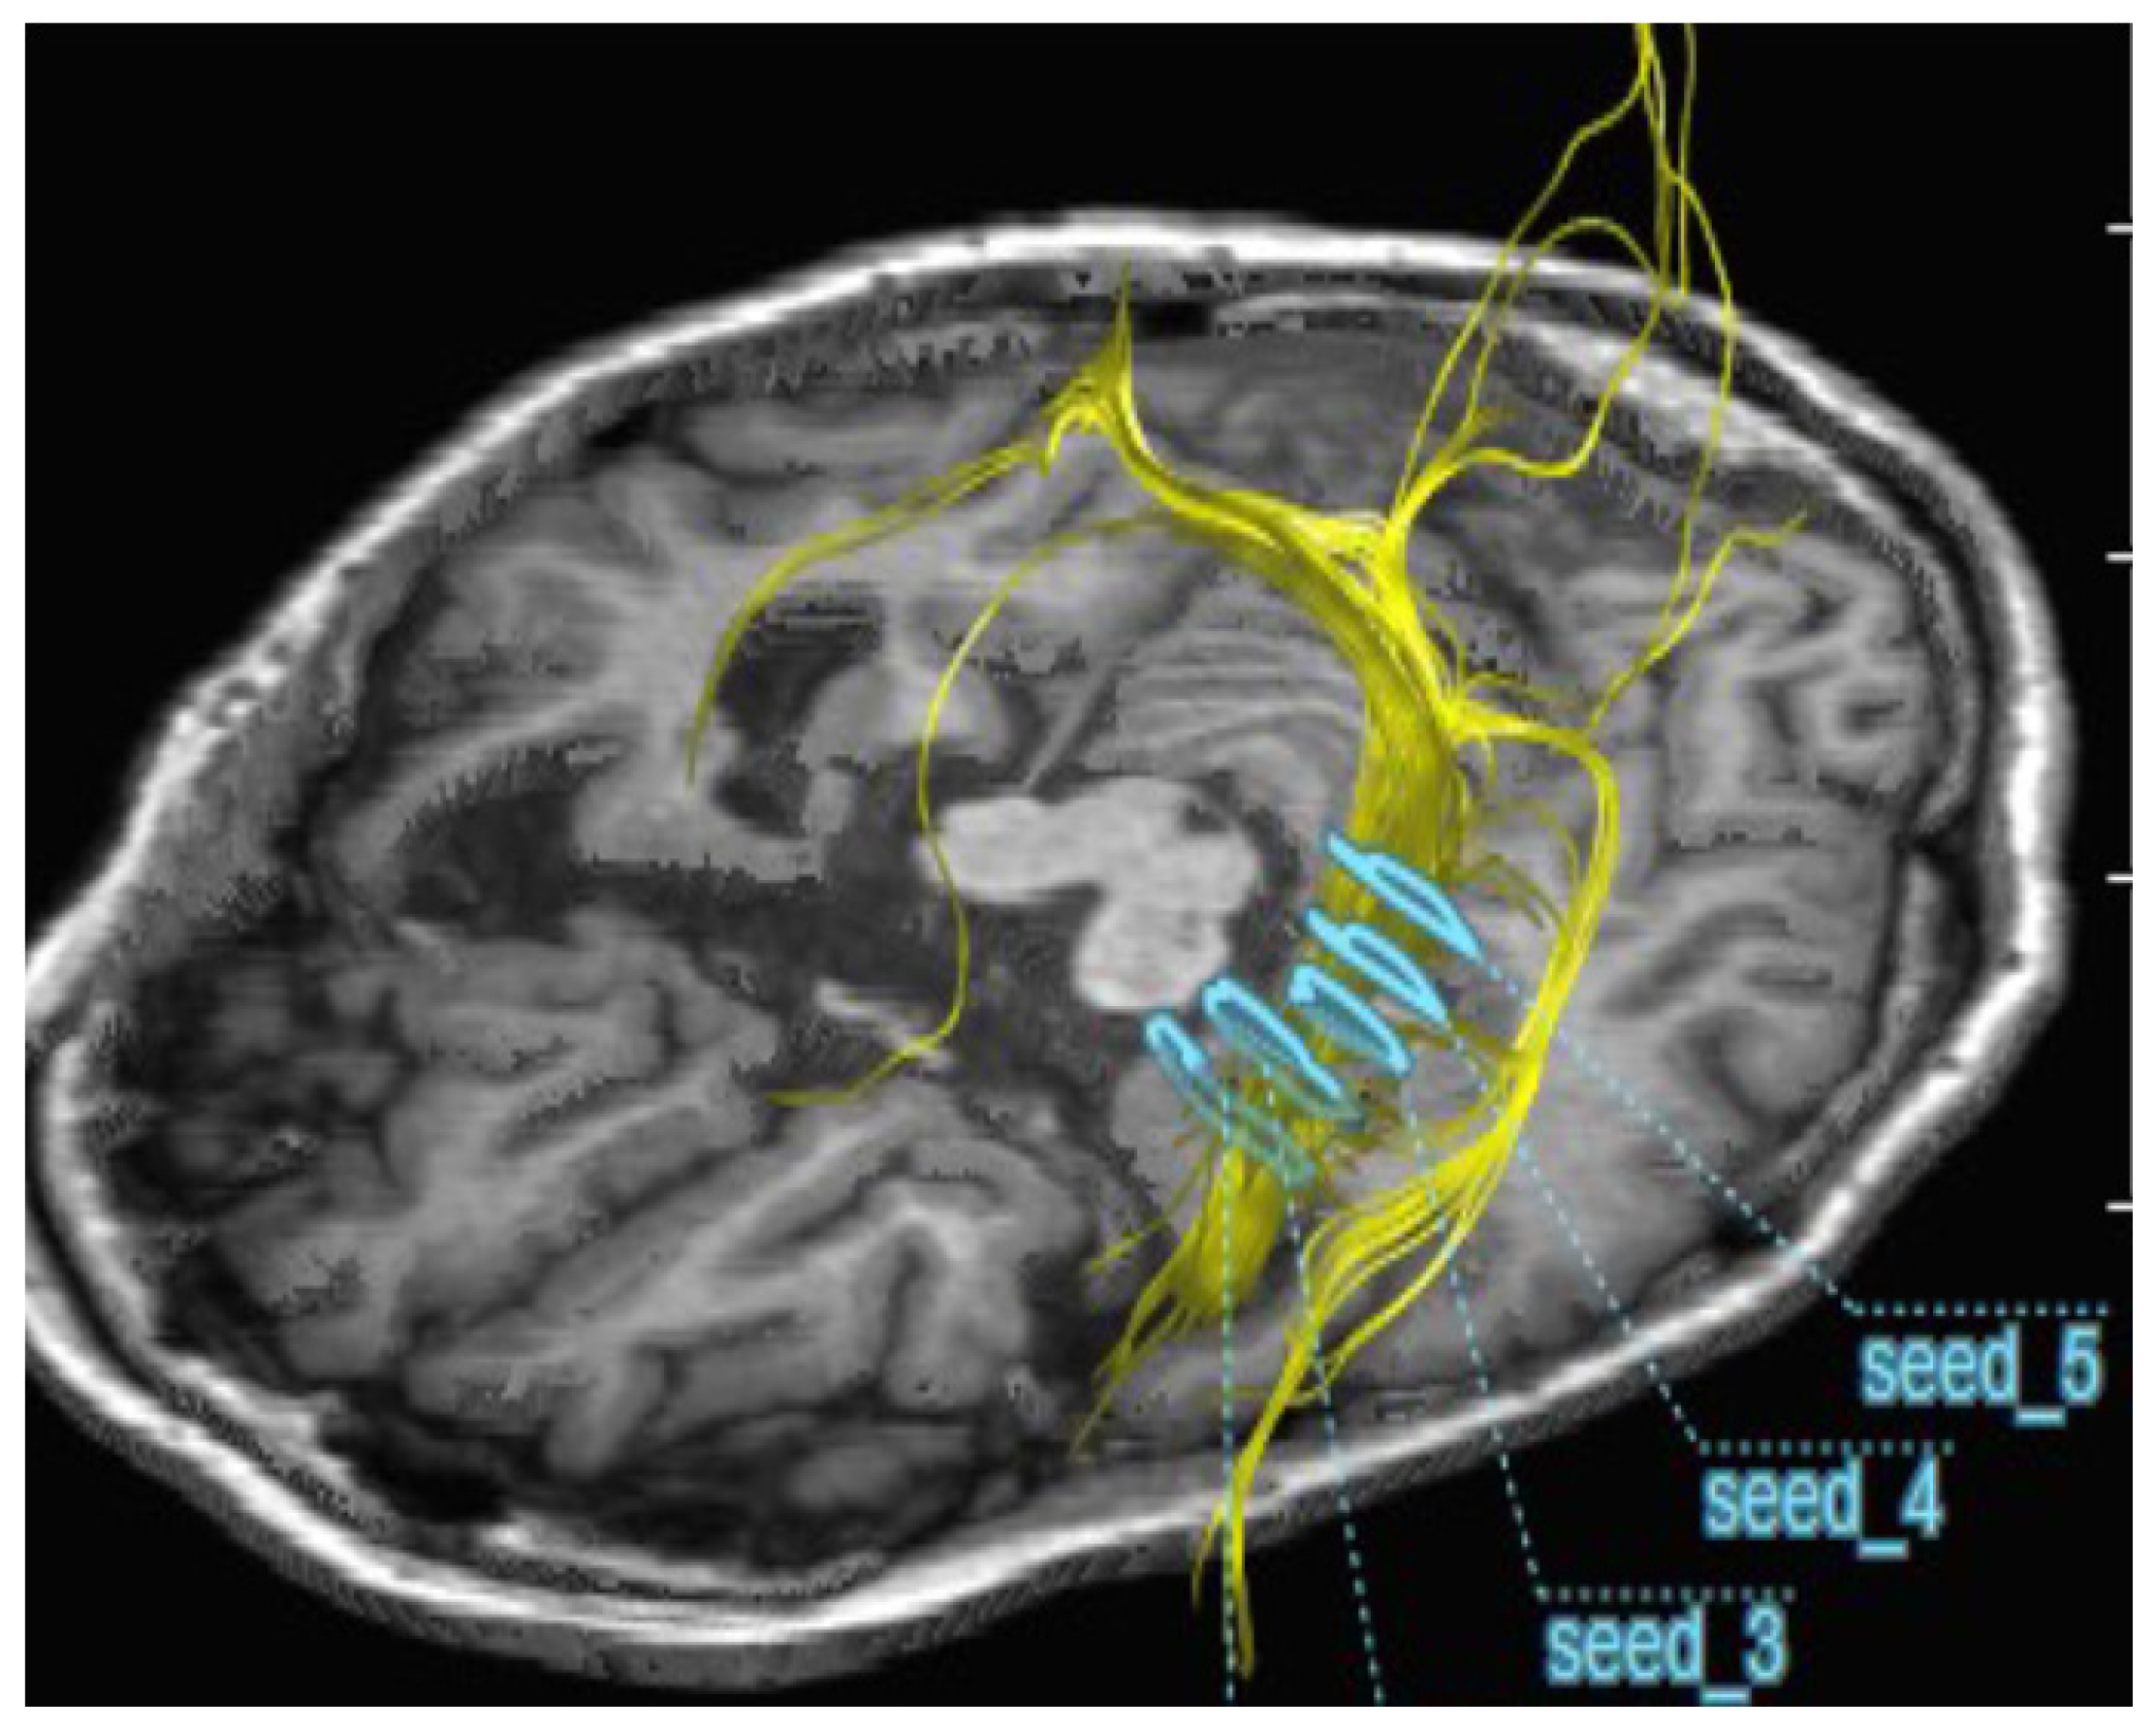

2.2. Improvement of Neurons by H2 Inhalation as Assessed by Diffusion Tensor Imaging

4.6. Measurement of the Integrity of Neurons by Diffusion Tensor Imaging